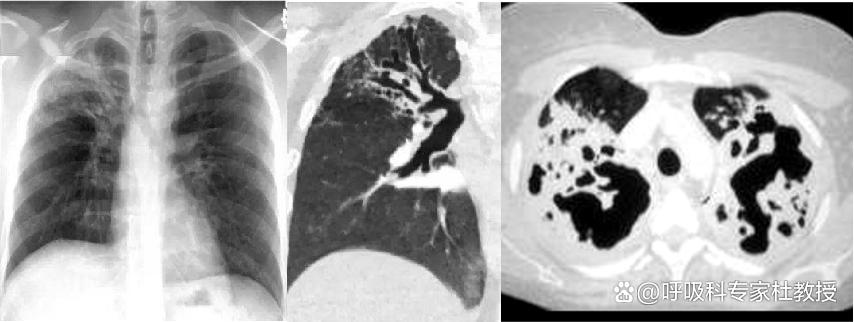

四、蜂窝征:扩张的支气管呈囊袋装,如葡萄一样成团出现,像蜂窝一样,囊内可因有液体存在而出现气液平面。

五、牵拉征:因支气管周围存在纤维化病变,瘢痕组织挛缩牵拉引起,往往扩张不均匀,边缘凹凸,且较为僵硬,与静脉曲张型不同。